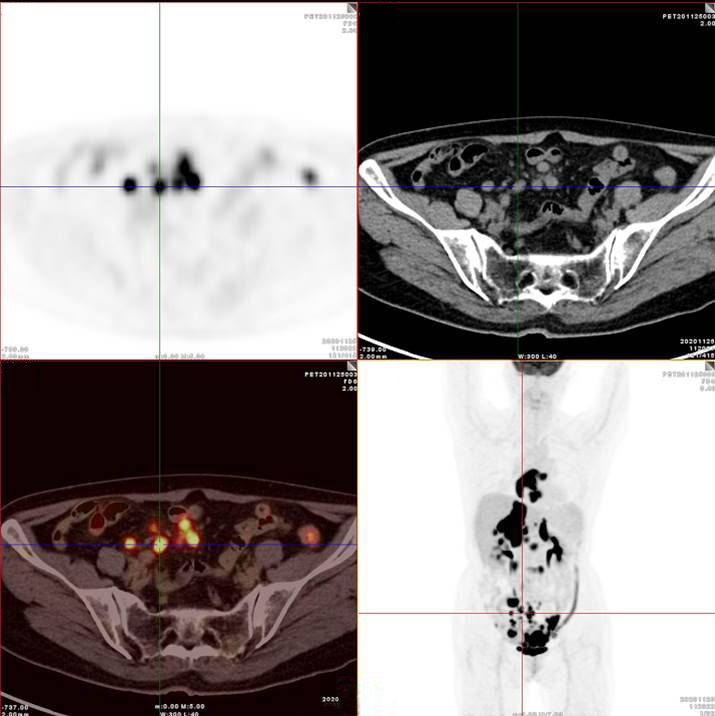

PET/CT影像圖

腸系膜多發(fā)淋巴結(jié)放射性攝取增高

多段小腸腸管放射性攝取增高